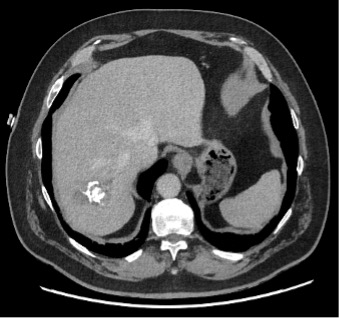

Ce CT-scanner, initialement réalisé chez une patiente de 70 ans à la recherche d’une dissection aortique scanner, met fortuitement en évidence une lésion hépatique.

Les douleurs de la patiente ont bien évolué sous traitement symptomatique. Son bilan sanguin avec FSS, CRP, tests hépatiques et pancréatique est dans la norme. Au vu de la présence de lésions kystiques hépatiques présentant des calcifications et des zones de nécrose sur le scanner, une sérologie pour l’échinococcose alvéolaire (EA) est demandée.